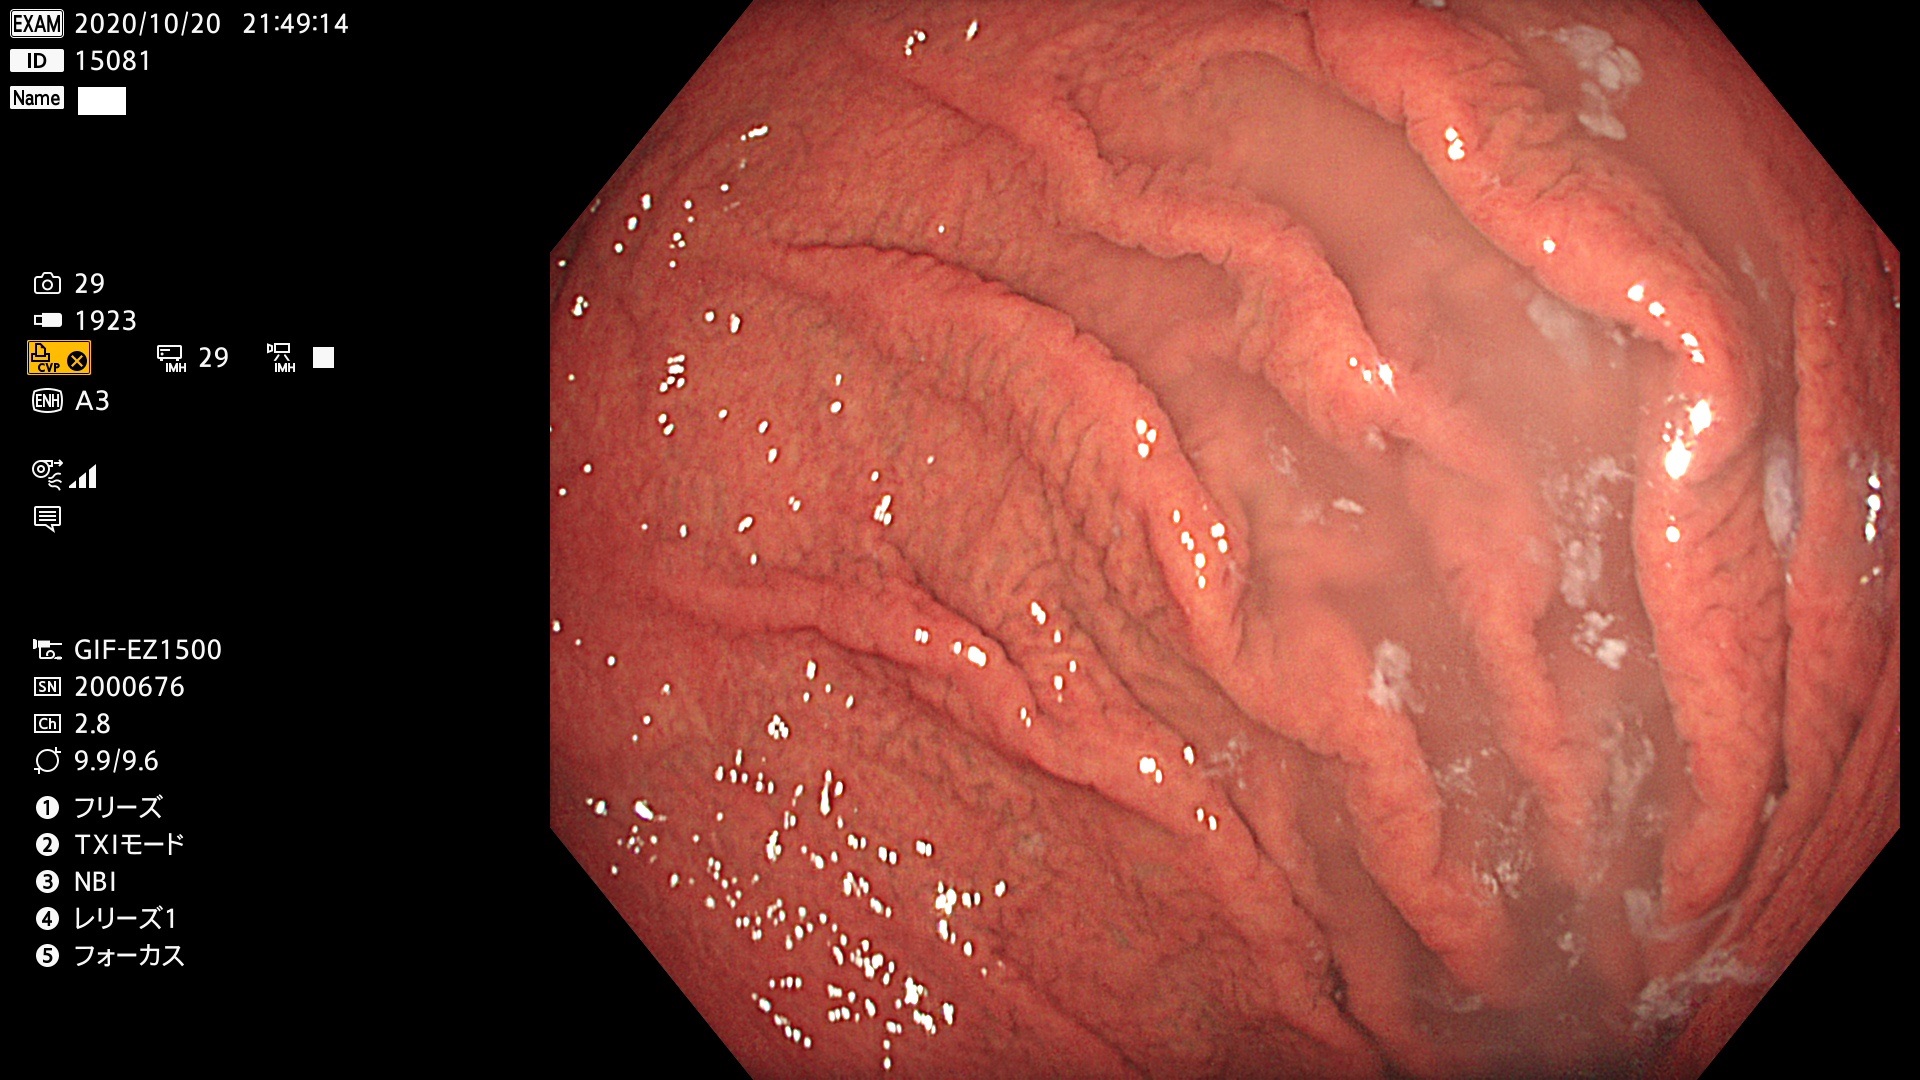

新型・胃カメラ(1500型)の画像

私は、オリンパスの最初の電子スコープ(100型)から代々、使用していますが今回のモデルチェンジが(開発期間が長いからですが)最も画質の向上が著明と感じました。正確に4K解像度(3840X2160)ではないのですが従来の機種(290型)のハイビジョン画質(約1000X1000)を遥かに凌ぐ画質であることは確かです。残念ながら、この画質をWEBやUSB保存画像で確認することはできません。内視鏡の画像レコーダーが2K(1280X720)までしか対応していないため「2Kにダウンコンバート」して保存されるからです。検査室には2台の4Kモニターが設置されていますので検査中に「4K内視鏡」を御確認下さい。